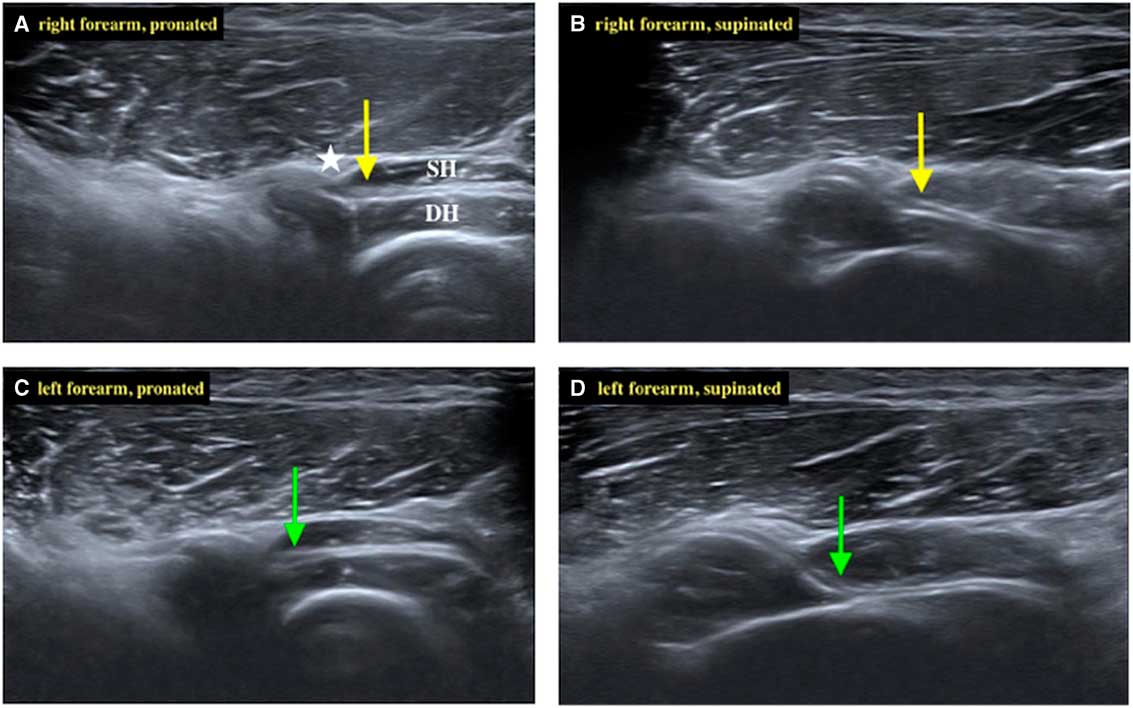

Ultrasonography was performed with an 18-MHz linear array transducer (Acuson S2000 Ultrasound System; Siemens, Munich, Germany). The probe was placed in parallel to the posterior interosseous nerve (PIN) and the PIN was examined with the forearm in the pronated and supinated positions, bilaterally, as shown in Figure 1. Compared with the right side, the left PIN showed marked compression and angulation by the superficial head of the supinator muscle in the supinated position. In-plane ultrasound-guided PIN hydrodissection was performed with a mixture of 0.5 ml 50% glucose water and 4.5 ml 1% xylocaine (Figure 2). The patient was also instructed to take oral hypoglycemic agents regularly and avoid strenuous or repetitive forearm activities.

Figure 1 The posterior interosseous nerve (PIN; arrow) penetrated between the superficial head (SH) and deep head (DH) of the supinator muscle. The arcade of Fröhse (asterisk) was depicted clearly under ultrasound. (A) The right PIN (yellow arrow) of the forearm in the pronated position. (B) While the right forearm was supinated, the right PIN remained relatively straight. (C) The left PIN (green arrow) of the forearm in the pronated position. (D) While the left forearm was supinated gradually, the left PIN became compressed and angulated.

Recently, high-resolution ultrasonography has been gaining popularity in assessing peripheral entrapment neuropathies. It has been reported that when PINs are found to be compressed at the arcade of Fröhse, they show a proximal swelling to up to 2 to 3.3 mm, compared with 1.1 to 1.3 mm in healthy subjects.Reference Bodner, Harpf, Meirer, Gardetto, Kovacs and Gruber 4 , Reference Djurdjevic, Loizides, Löscher, Gruber, Plaikner and Peer 5 However, considerable statistical error exists while measuring PIN diameter because of its small size and its normally tapering shape.Reference Dong, Jamadar and Robertson 6 In our case, the PIN did not show marked swelling, but there was obvious compression and angulation by the superficial head of the supinator muscle. Similar findings were reported by Kowalska et al.Reference Kowalska 3 We agree with the authors that PIN angulation might be a better ultrasound diagnostic criterion instead of PIN proximal swelling for diagnosing supinator syndrome.